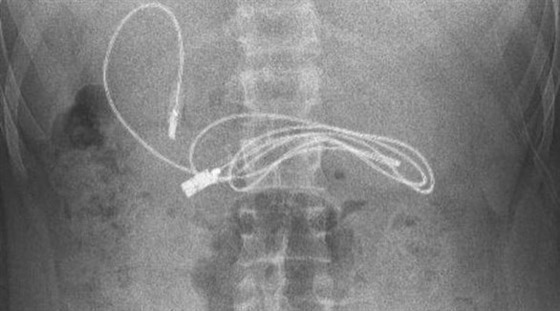

صدم مراهق الأطباء، بعد نقله إلى أحد مستشفيات تركيا وهو يعاني من غثيان شديد وآلام مبرحة في معدته، إذ أظهرت الأشعة المقطعية، ابتلاعه سلك شاحن طوله 90 صنتيمتراً. وخضع المراهق الذي لم تكشف هويته، إلى عملية عاجلة لاستخراج السلك من معدته، ليتبين أنه ابتلع ربطة شعر، أيضاً.

وقال الطبيب الذي أشرف على الجراحة، إن العملية كانت معقدة لأن أحد طرفي السلك مَر إلى الأمعاء الدقيقة. ولحسن الحظ، تعافى المراهق، 15 عاماً، سريعاً بعد العملية وعاد إلى منزله في ديار بكر بصحة جيدة.